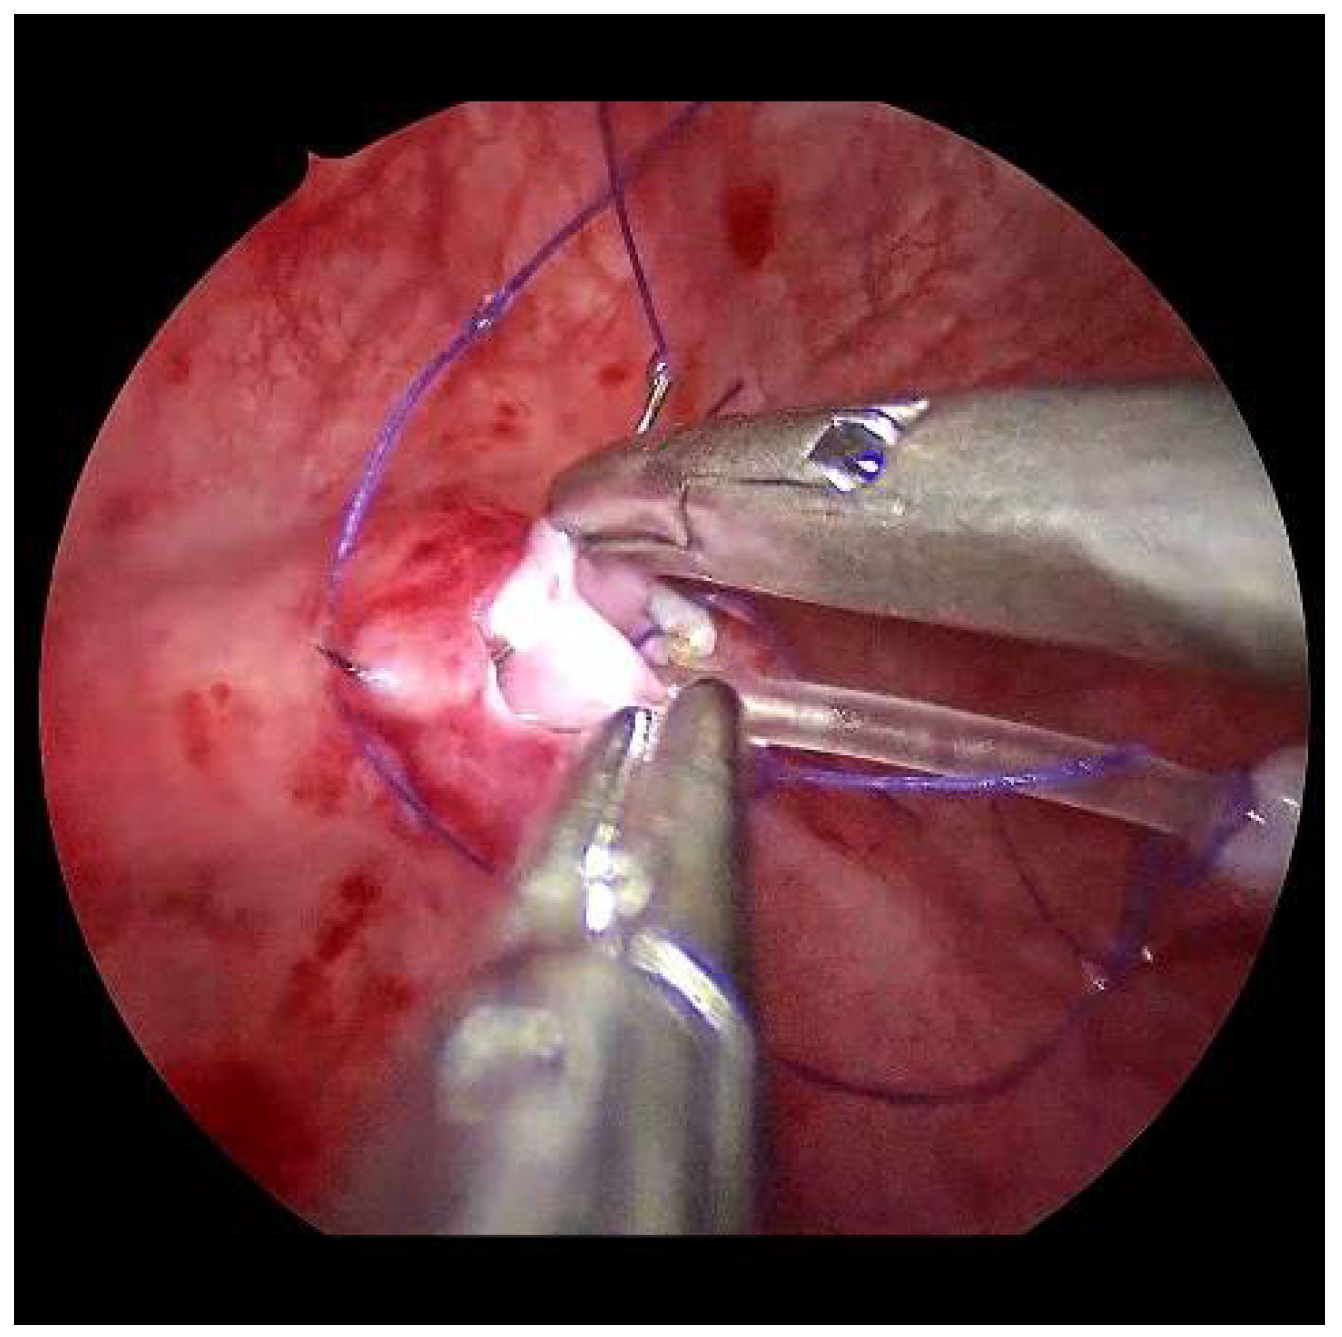

Now, the ureter is intubated with a 3 or 4 Fr. silicone tube, followed by subtle circumferential electrical mucosa incision with a fine dissecting needle (Figure 3). The ureteral release is continued using an electrical hook for at least 4 to 6 cm until it can be positioned without tension to the opposite ostium (Figure 4). Duplicate ureters are intubated twice and mobilized together. If bilateral, the submucosal tunnel is created between the two ostial incisions. If not, an additional mucosal incision is made 1 cm canially of the opposite regular ostium (Figure 5).

Figure 3.

For a left-sided VCUR, the ostium is circumferentially incised with a fine needle while gently pulling on the intubated left ureter.